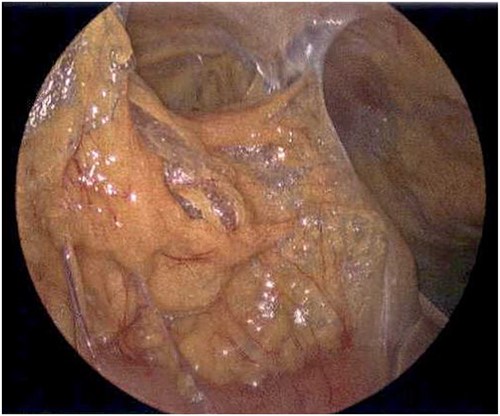

On Hospital Day 2, an interval CXR showed continued resolution of the right-sided pneumothorax but worsening subcutaneous emphysema of the bilateral chest wall and pneumoperitoneum (Fig. 3). Surgical consultation was sought, leading to diagnostic laparoscopy. In the abdomen, emphysematous changes within the gastrohepatic ligament and omental adhesions to the anterior abdominal wall were visualized (Figs 5 and 6). Laparoscopic exploration revealed no diaphragmatic injury or perforated viscera but identified emphysematous changes throughout the preperitoneal space, small and large bowel mesentery, and right paracolic gutter (Figs 7 and 8). Immediate post-op CXR no longer showed evidence of pneumoperitoneum (Fig. 4). The patient was transferred back to the ICU and extubated after three days on Day 5. After the removal of chest tube and transfer to a medical floor on Day 8, the patient developed aspiration pneumonia that was treated with antibiotics. She was discharged on Day 15.

Laparoscope revealing emphysematous changes within the gastrohepatic ligament.